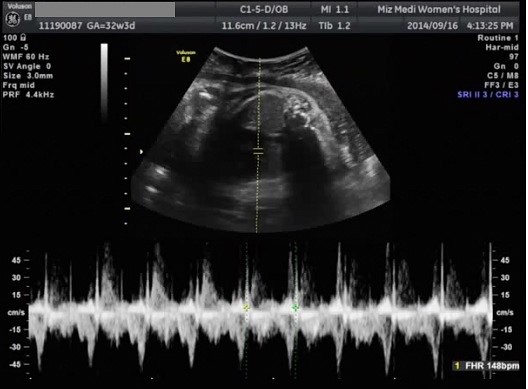

[태아초음파 동영상7] 미즈메디 후기 정밀초음파 동영상/ 긴장했던 후기 정밀 초음파

32주 3일 미즈메디에서 후기 정말 초음파 했어요. 딱 10주전에 중기 정밀 초음파를 봤...